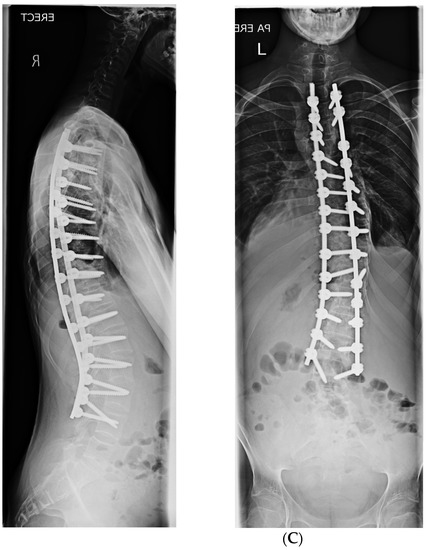

2. Materials and Methods

3. Results

3.1. Coronal Plane Correction

3.2. Sagittal Plane Correction Parameters